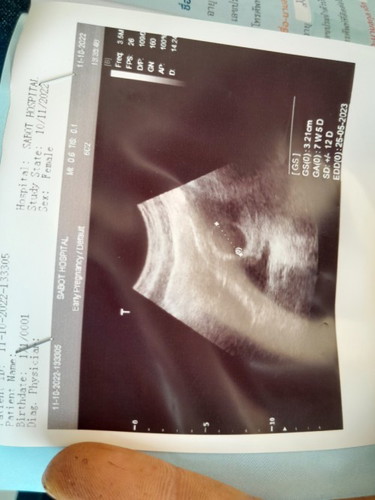

ท้องแรกที่มีความกังวลใจ

จาก 8 weekที่ได้เห็นถุงตั้งครรภ์คุณหมอบอกมีภาวะท้องลมแม่เครียดมาก มาวันนี้11 week 6 Day ได้เจอกันสักที กว่าจะได้เจอแม่ลุ้นตลอดตอนหมอซาว